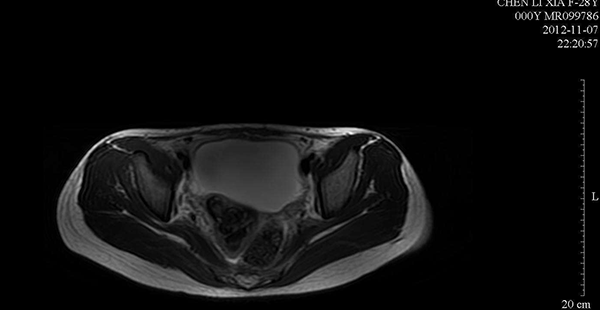

宫腔积液检查结果(示例)

B超检查下的盆腔积液